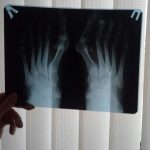

По их стопам

Что делать тем, кто страдает от «халюс вальгус»?

Наступила зима. Все мы прекрасно знаем, насколько непросто на это время года подобрать удобную и одновременно красивую...